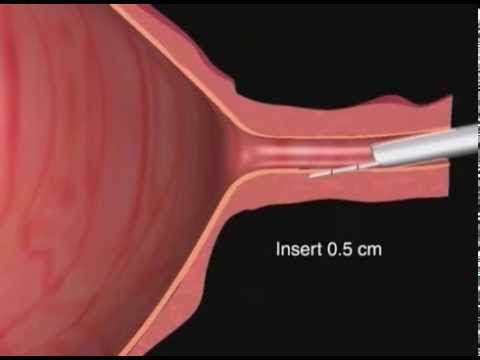

The urethra is a tube connected to the bladder. Urine is held in the bladder until it becomes full and then it travels through the urethral opening to be released from the body. Its anatomy is different in men and women. One of the most common differences is that men have longer urethras than do women. Possible problems can include pain, infections, and cancer.

Generally, all humans have urethras. In men, the structure is part of the reproductive system. Located in the penis, it transports urine and semen from the body. This tube in males typically measures about eight inches (about 20.3 cm) long.

In women, the urethra generally is about 1.5 inches (about 3.8 cm) long. Unlike males, it is not part of the female reproductive system. Instead, it is located above the opening of the vagina, within the labia minora. Its only purpose in women is to serve as an exit site for urine.

In women, the urethra generally is about 1.5 inches (about 3.8 cm) long. Unlike males, it is not part of the female reproductive system. Instead, it is located above the opening of the vagina, within the labia minora. Its only purpose in women is to serve as an exit site for urine.

This tube in males typically measures about eight inches (about 20.3 cm) long. An enlarged prostate may be a symptom of urethral strictures. In women, the urethra generally is about 1.5 inches (about 3.8 cm) long. Unlike males, it is not part of the female reproductive system.